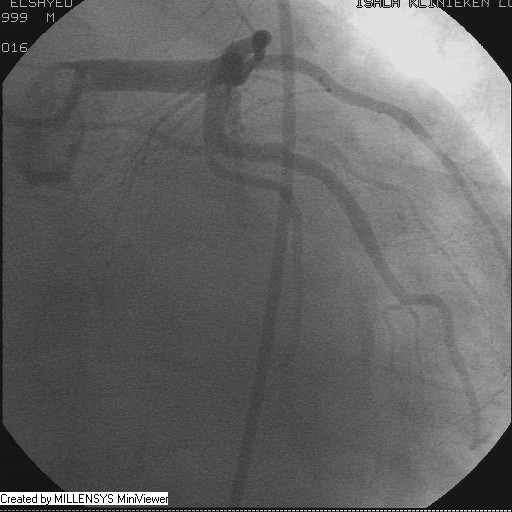

Patient transfered to Cardiac Catheterization Laboratory, coronary angiography showed atherosclerotic coronaries but without significant lesions, especially LAD that was patent with TIMI 3 flow (Figure 1- 5). Re-evaluation of the Angiography showed a small stump that can be for an occluded 1st diagonal (Figure 2a), at that level the LAD has a non-significant lesion.

Figure 3

Figure 4